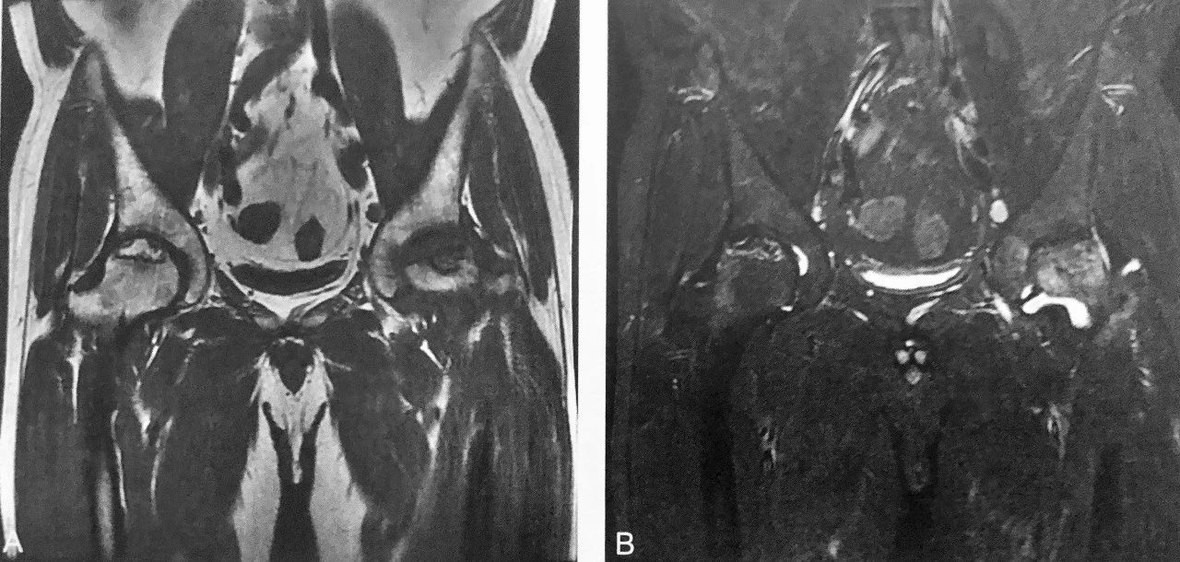

圆 点 征

A.腰椎 CT 轴位示椎体内片状低密度区内多发点状高密度影,类似圆点形(箭头);B.T2WI 轴位示椎体内片状稍高信号区内多发点状低信号灶(箭头);C.腰椎 CT 重建矢状位示椎体内骨小梁条状增粗,周围间隔低密度区,呈“栅栏征”改变(箭头);D~E.T1WI 及T2wI 示椎体内片状稍长T2、稍短T1信号,病灶中心及周边见小点状、条状低信号区(箭头)

判读要点:

1、是椎体血管瘤特异性影像征象;

2、在 CT 轴位图像观察,呈圆点样高密度,周围脂肪样低密度;CT 矢状位或冠状位呈灯芯绒征或栅栏征;

3、MRI 有助于观察增粗骨小梁周围脂肪结构。